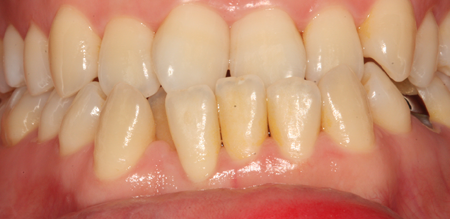

치주치료

청담네오플란트는 치주치료를 통하여 치아를 살릴 수 있는 기회를 놓치지 않습니다.

치주염(잇몸병)은 치아에 붙어있는 치석 및 세균 등에 의한 염증반응으로 잇몸뼈가 상실되는 질환을 말합니다.

초기에는 잇몸이 붓거나 잇몸에서 피가 나는 증상이 나타나며 계속 방치하면 치아를 발치해야 할 수도 있습니다.

치주치료는 이러한 치석 및 세균 등을 제거하여 잇몸뼈를 안정된 상태로 유지하는 시술을 말하며, 청담네오플란트에서는 치의학박사 / 전문의가 직접 시술하고 있습니다.

치주염 단계별 증상

건강한 상태

치아 주위의 잇몸이 핑크색을 띄며, 잇몸에서 피가 나지 않음.

스케일링을 6개월 ~ 1년 주기로 받고 올바른 칫솔질로 건강한 치주 조직을 유지

치은염 (초기~중기)

치아 주위의 잇몸이 붉게 부어 있으며, 칫솔질 등을 할 때 피가 남.

스케일링 주기의 조절이 필요할 수 있으며, 올바른 칫솔질을 시행하여야 함.

치주염 (중기~말기)

주기적으로 잇몸이 붓고 피가 나며, 욱씬하거나 우리한 통증이 나타남.

치주치료 및 정도에 따라 치주수술(잇몸수술)이 필요함. 향후 관리 정도에 따라 3~6개월 간격으로 내원하여 유지치료를 시행하여야 함.

치주염 (말기)

잇몸이 항상 부어 있으며, 이가

흔들리는 정도가 점점 심해짐.

치주치료가 필요하며, 정도에 따라 치아를 발치하여야 할 수 있음.

치주치료 전후사진